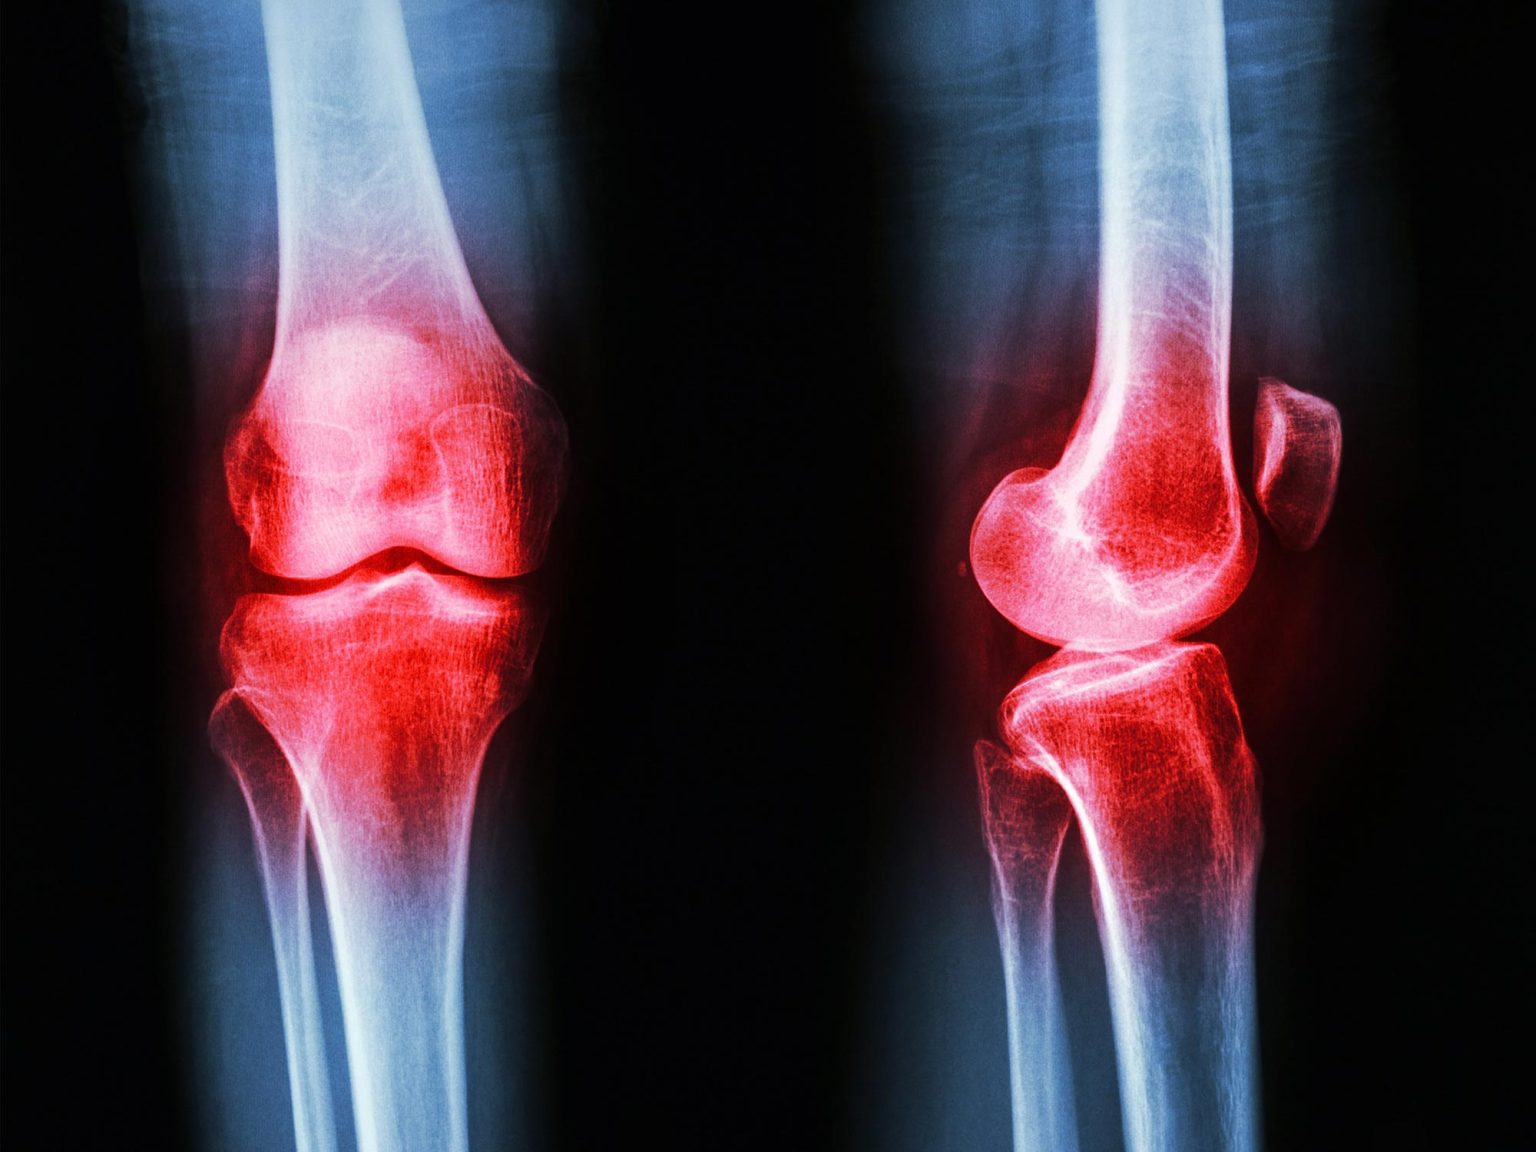

Ревматоїдний артрит (РА) — хронічне системне аутоімунне захворювання, що уражає ~1% населення Землі (~20 мільйонів людей). Його суть: імунна система атакує синовіальну оболонку суглобів — і запалення поступово руйнує хрящ і кістку. Поточне лікування включає метотрексат, біологічні агенти та глюкокортикоїди — ефективні, але з тяжкими побічними ефектами при тривалому застосуванні. Пошук нових мішеней і речовин із природних джерел є одним із головних напрямів ревматологічних досліджень.